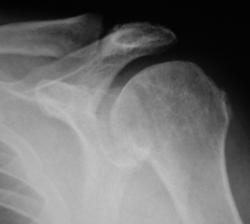

Иллюстрация 1 и 2. Рентгенограмма и фрагмент рентгенограммы с увеличением. В области головки плечевой кости определяются нерезко очерченные участки намечающегося остеопороза. Визуализируется нечеткость контура головки плечевой кости по латеральному контуру, в области большого бугорка. Определяется перестройка структуры костной ткани в области дистального отдела акромиального отростка лопатки. По верхнему краю определяется неровность и нечеткость контура. Решено произвести томографическое исследование.